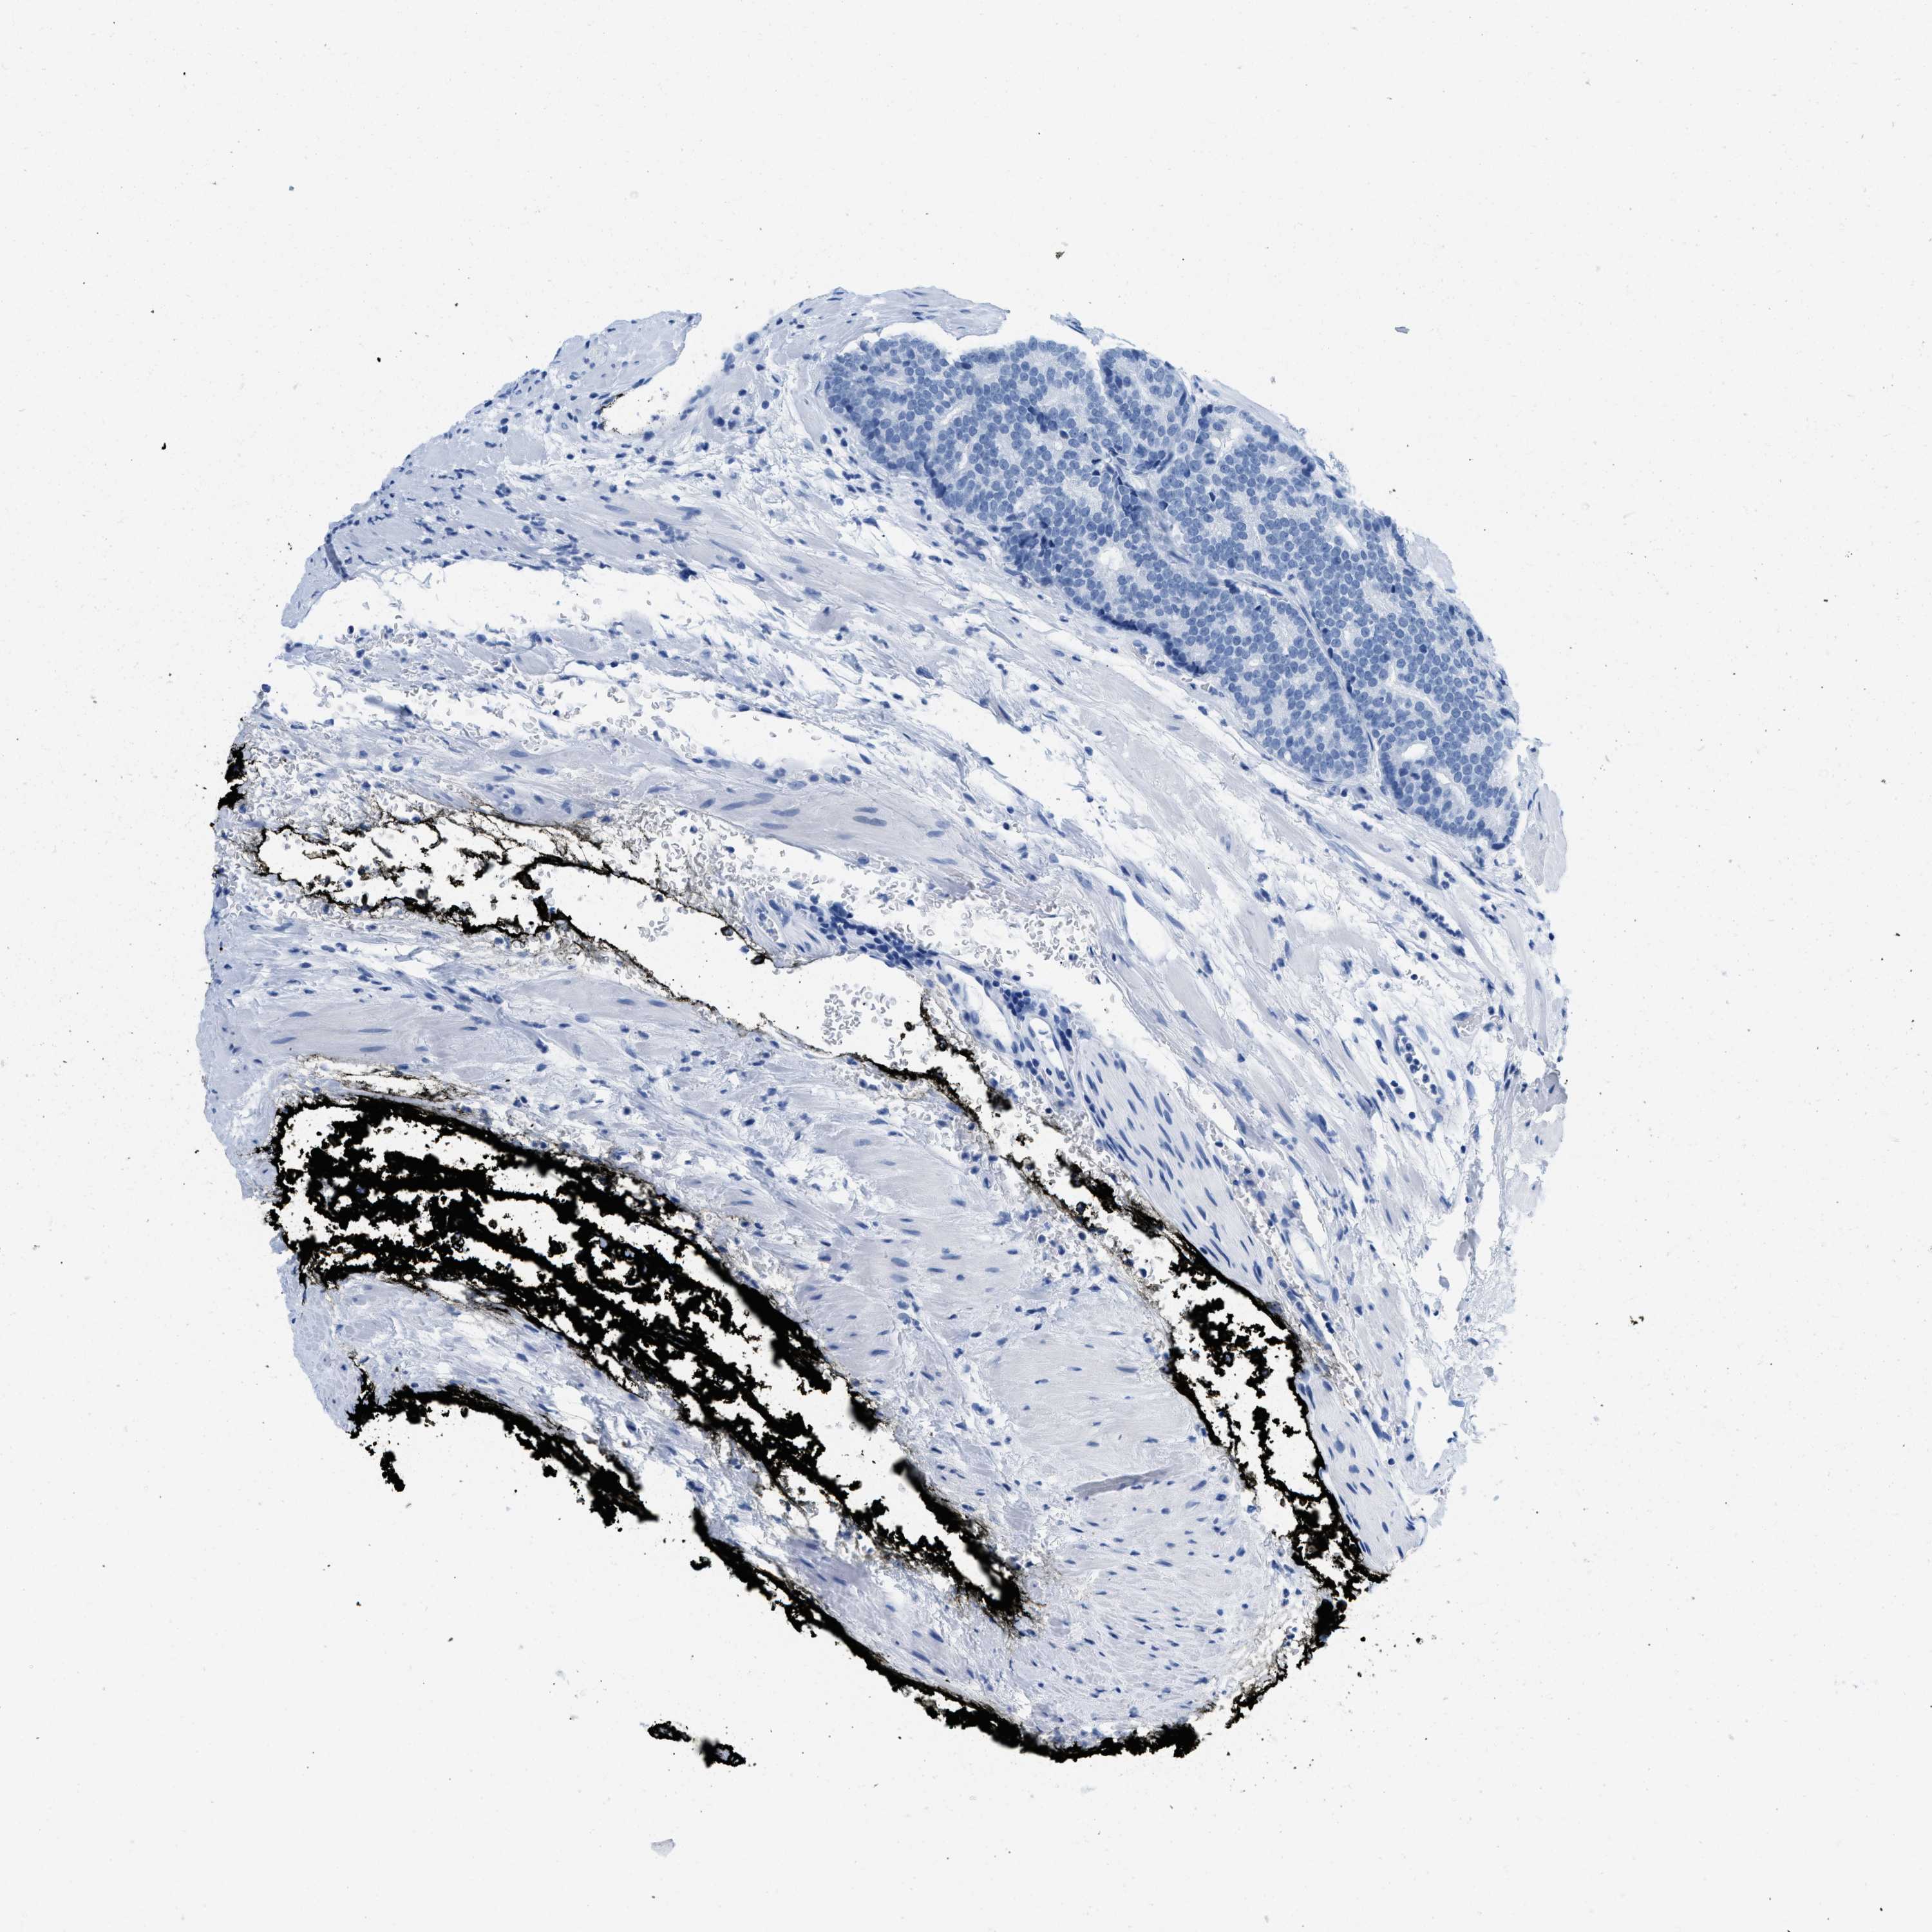

PROSTATE CANCER - Protein expressioni

A mouse-over function shows sample information and annotation data. Click on an image to view it in a full screen mode. Samples can be filtered based on level of antibody staining by selecting one or several of the following categories: high, medium, low and not detected. The assay and annotation is described here.

Antibody stainingi

Antibody staining in the annotated cell types in the current human tissue is reported as not detected, low, medium, or high, based on conventional immunohistochemistry profiling in selected tissues. This score is based on the combination of the staining intensity and fraction of stained cells.

Each image is clickable and will lead to virtual microscopy that enables deeper exploration of all samples and also displays staining intensity scores, fraction scores and subcellular localization as well as patient and tissue information for each sample.

Antibody HPA054026

Antibody CAB010823

Antibody CAB016728

Antibody CAB036009

Staining

High

Medium

Low

Not detected

Intensity

Strong

Moderate

Weak

Negative

Quantity

>75%

75%-25%

<25%

None

Location

Nuclear

Cytoplasmic/membranous

Cytoplasmic/membranous,nuclear

Adenocarcinoma, High grade

Adenocarcinoma, Low grade